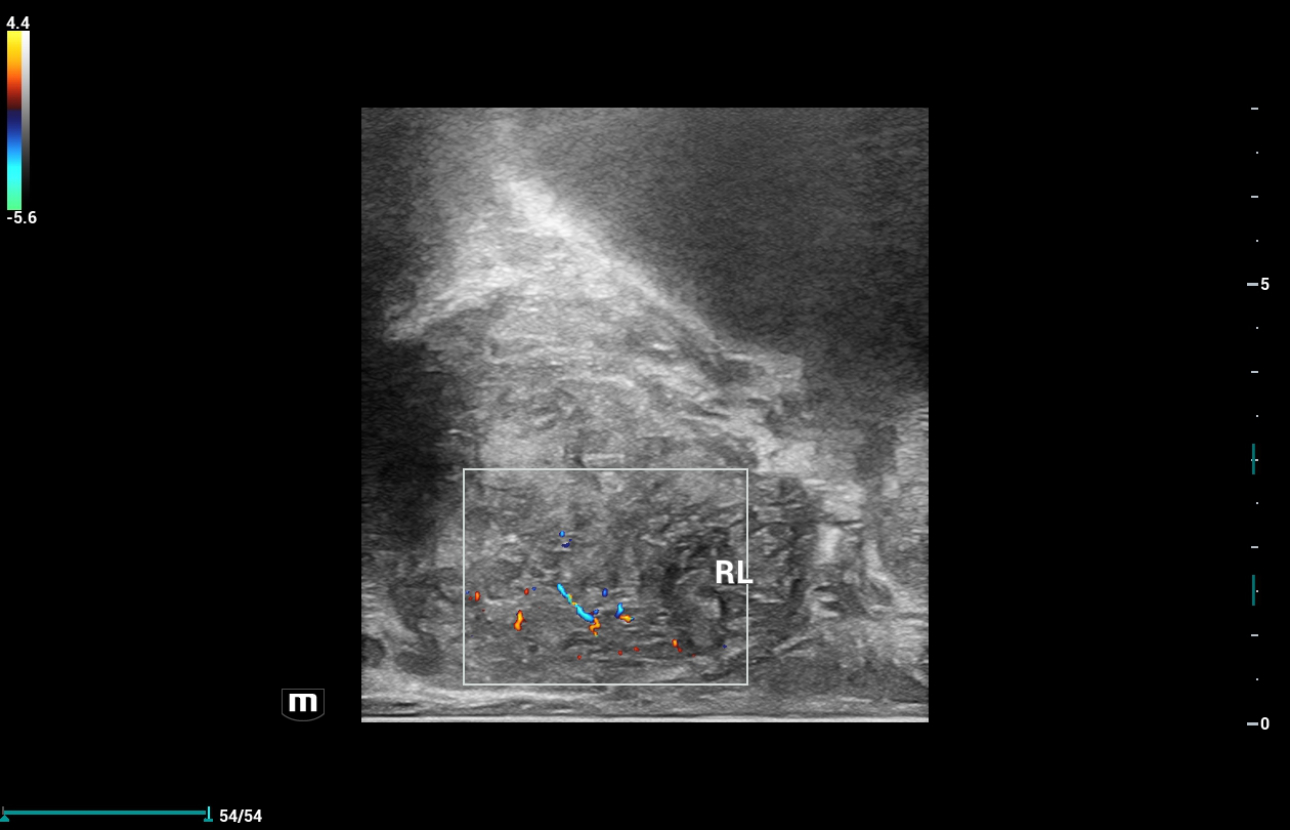

2D color ??? ??:

???? ??? ??? ?? ?? ??? Biplane endocavitary transducer ( ????? Resona i9, ELC13-4)? ??? ??? ??? ?????.

??? ??? ????? ?? ?? ??-?? ??? ???? ???? ???????. ????? ?? ??? ?? ?? 2?? ??? ???? ???, ???? ???? ?????, ???? ????? ????? ??? ?? ? ?????. ???? ???????(NTE: Natural Touch Elastography)? 2D ?? ?? ???(STE: Sound Touch Elastography)? ??? ??????? ??? ?? ??? ????? ?? ???????.

2D color ???? RL?? ???? ? ?? ????? ???? ??? ??? ?? ????, ?? ????? ??????? ?? ??? ?? ??? ???? ??? ?? ?? ??? ??? ????? ?????, ???? ????? ???? ???? ??????.